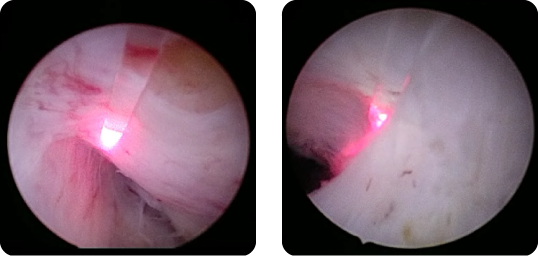

泌尿器科学会の推奨する尿路結石治療ガイドラインに準じて治療オプションの提示・決定を原則としています。尿路結石には体外衝撃波結石破砕術や内視鏡を使った手術を行っており、多くは通院治療で行っています。体外衝撃波では治療困難な症例に対しては内視鏡手術(経尿道的腎尿管砕石術)を施行します。ホルミウムレーザー砕石装置および細径内視鏡が導入されており、内視鏡手術の安全性と有効性が高くなっています。